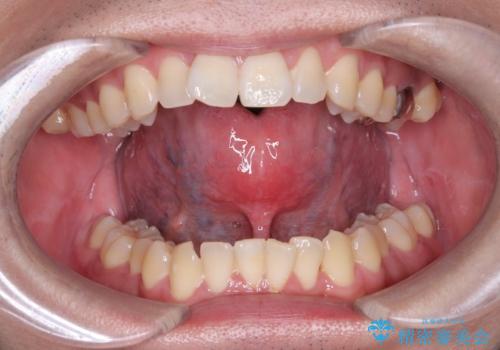

舌小帯の形成術を行い、舌の可動域を広げました。

手術後は、通常、数日から数週間で回復します。痛みや腫れがある場合は、医師の指示に従って適切な処置を行います。